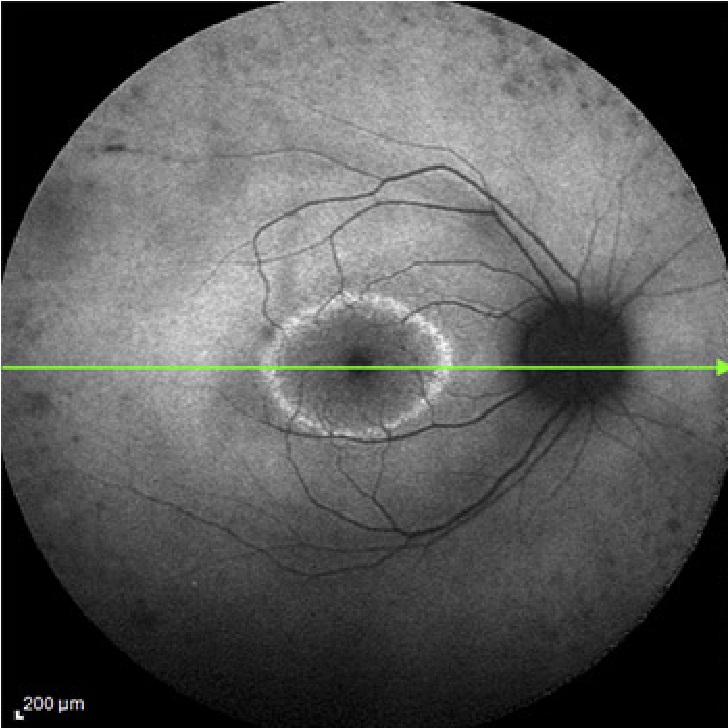

Tomografía de Coherencia Óptica (OCT)

Examen de la retina (retinografía)